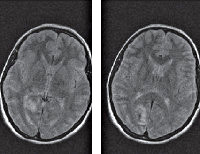

• МРТ головного мозга. Визуализирует зону острых ишемических изменений. У пациентов с большим стажем мигрени возможна диагностика «старых» очагов ишемии, лакунарных инфарктов, атрофических процессов. По показаниям МРТ заменяют КТ, МСКТ головного мозга.